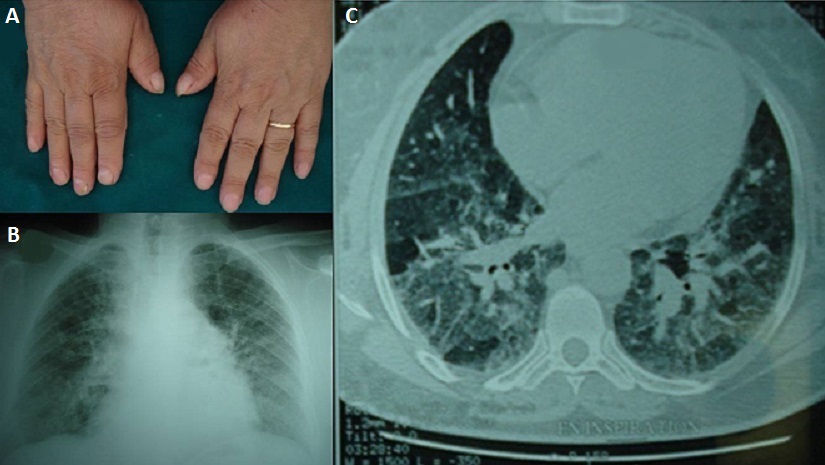

La maladie du poumon des éleveurs d'oiseaux est une alvéolite d'hypersensibilité secondaire à l’inhalation d’allergène d’origine aviaire (plumes et déjections d’oiseaux). Elle peut se manifester sous 3 formes (aiguë, subaiguë et chronique). Patiente âgée de 54 ans, se présentait pour dyspnée d’effort et toux sèche évoluant depuis une année. L’examen clinique objectivait un hippocratisme digital bilatéral (A). Il existait des râles crépitants à l’auscultation. Le bilan biologique montrait un syndrome inflammatoire, une hyperleucocytose modérée et une hypergammaglobulinémie polyclonale à 15,6 g/L. Le cliché thoracique révélait un syndrome interstitiel avec un aspect flou des 2 champs pulmonaires (B). Le scanner thoracique objectivait une pneumopathie interstitielle diffuse avec un épaississement des lignes septales et des hyperdensités en verre dépoli diffuse (C). L’exploration fonctionnelle respiratoire mettait en évidence un trouble ventilatoire restrictif avec une baisse de la capacité vitale de 35%. La gazométrie artérielle au repos a retrouvé une hypoxémie à 55 mmHg de PaO2. L’interrogatoire poussé nous fait découvrir la notion d’élevage domestique de pigeons et de perroquets depuis 10 ans. Après avoir éliminé les autres causes de pneumopathies interstitielles (biopsie des glandes salivaires accessoires normale, dosage de l’Enzyme de conversion de l’angiotensine normal, enquête infectieuse avec Recherche de BK négative), le diagnostic de la maladie des éleveurs d’oiseaux étaient retenu. La patiente a été traitée par corticothérapie orale (1 mg/Kg/j) avec l’éviction totale de l’exposition. L’évolution était favorable, avec diminution de l’intensité de la dyspnée, de la toux et une stabilisation des lésions radiologiques.